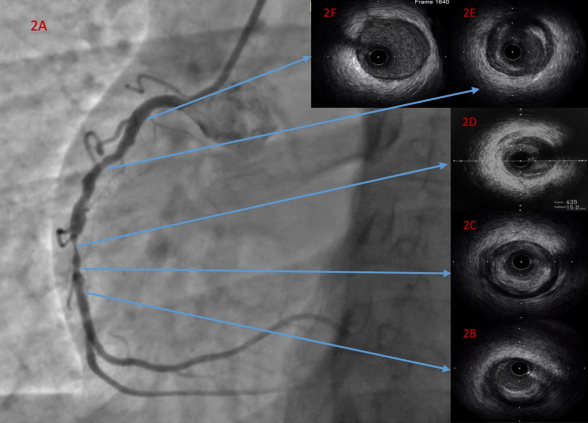

It was carried out a coronary angiogram that showed a no angiographic lesions in the left anterior descending and circumflex arteries, however the right coronary artery showed proximal non-significant irregular plaques, there was a 95% mid segment focal stenosis. Figure 2A. Taking into account that an acute MI is a rare condition in female young patients with no risk factors, and the elevated odds of spontaneous coronary artery dissection as cause of the acute coronary event based on the angiographic images, we decided to perform  intravascular ultrasound (IVUS) in the right coronary artery to understand the mechanism of this MI, guide the PCI, assess the final result and manage potential complications of the intervention.

The IVUS pullback assessment showed an extensive concentric plaque burden from distal to proximal segment of the right coronary artery (figures 2B, 2C, 2E and 2F), with a tight stenosis with concentric plaque and dissection at 5 o’clock at the site of the referred 95% stenosis (figure 2D).

Figure 2A. coronary angiogram RAO 30-degree view showing the angiographic lesions. 2B, 2C, 2D, 2E and 2F show the IVUS assessment.